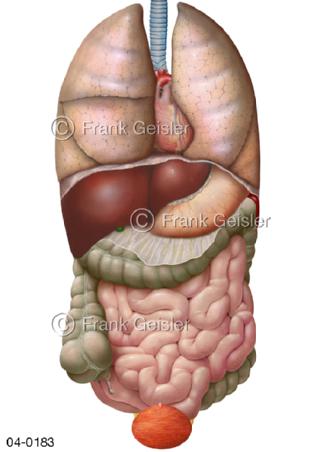

Bildergalerie Topografie Organe

Bilder zur topografischen Anatomie, die Lage der Organe und die Strukturen nach ihren räumlichen Lagebeziehungen zueinander, Übersicht der inneren Organe im Kopf und im Rumpf, Topografie der Organe im Brustraum (Thorax) und im Bauchraum (Abdomen)